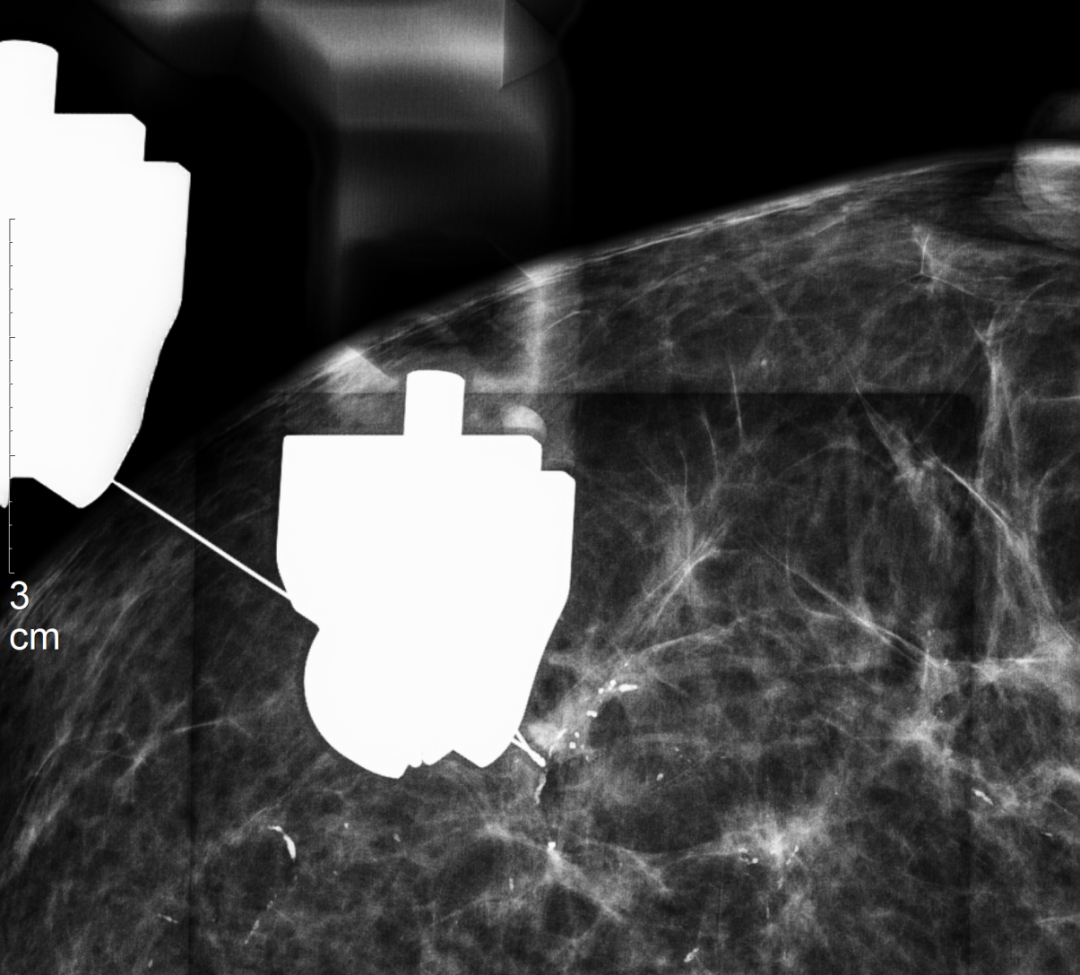

钩针末端的倒钩会固定在病灶周围组织中,从而为外科医生标记出病灶的准确位置。整个定位过程误差可控制在毫米级。

患者随后带着这根“导航针”进入手术室,外科医生便能据此快速、精准地找到并切除目标病灶。

怎么制造手术钩针狙击乳腺结节癌变!这种新技术专揪早期乳腺癌_https://www.jmylbn.com_新闻资讯_第8张

▲手术精准切除病灶(术后标本片),病理证实为乳腺导管原位癌

技术应用实例

近日,我院放射科与乳腺外科合作,成功开展了深圳西部地区首例“乳腺断层影像引导下钩针定位术”。这标志着我院在乳腺疾病精准诊疗领域的技术实力迈上新台阶,填补了区域内相关技术空白。